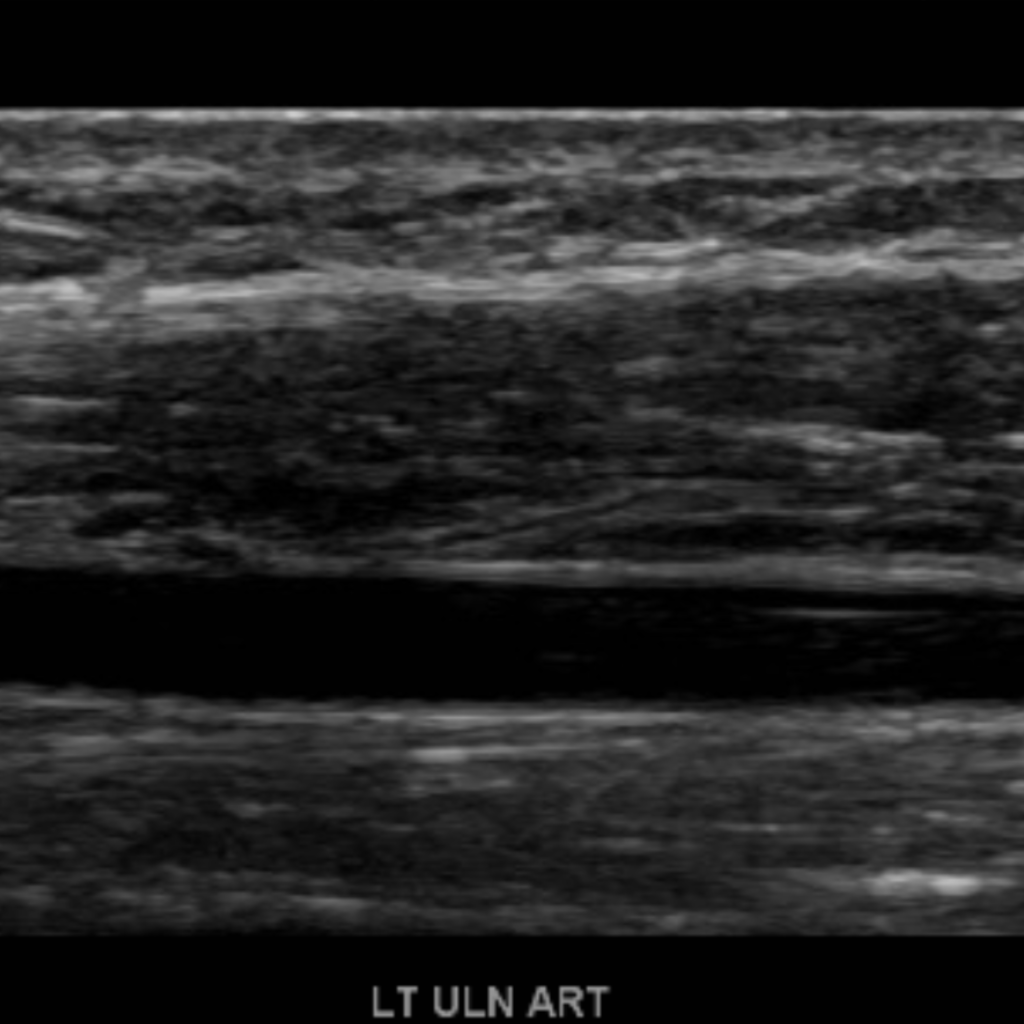

The subclavian artery arises from the brachiocephalic artery on the right and off of the aortic arch on the left. This artery further divides into the axillary, brachial, radial, ulnar, palmar and digital arteries respectively.